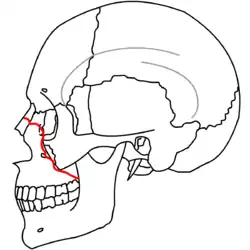

A principios del siglo XX, René Le Fort trazó ubicaciones típicas para las fracturas faciales, éstas ahora son conocidas como I, II y III fracturas de Le Fort (derecha).[5][2][6]

La Fractura de Le Fort#Lefort III, también llamada disyunción craneofacial y fractura facial transversal,[7][11] cruza la parte delantera del maxilar superior e implica al hueso lacrimal, a la lámina papirácea, y a la cavidad orbitaria, y a menudo implica al hueso etmoides,[9] es la más grave.[12] Las fracturas de Le Fort, que representan del 10% al 20% de las fracturas faciales, a menudo son asociadas con otras lesiones graves.[9]